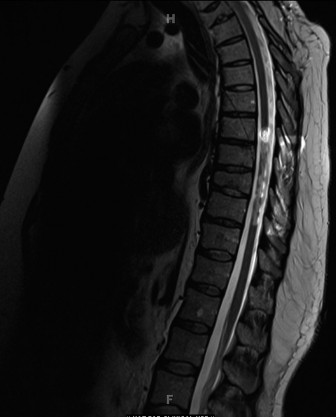

Plain radiographs were taken of the patient’s spine and displayed in Figure 10–20A and B.

Figure 10–20 A–B

Given the clinical and radiographic findings, what is the next step in management to definitively diagnose the patient?

The correct answer is (B). The patient’s clinical picture points toward a spinal cord injury, however the plain radiographs seen above show no evidence of any fractures or displacements. Detailed evaluation of the spinal cord and its surrounding paraspinal ligaments is needed in this case, of which only an MRI can reveal. A standard CT scan provides excellent bony detail but does not give much information about the spinal cord unless a CT myelogram is obtained. Given the patient’s clinical findings, obtaining bending radiographs in a potentially unstable spine is not recommended. EMG and nerve conduction studies are not indicated in this patient.

An MRI is obtained and a sagittal view is displayed in Figure 10–21.

Figure 10–21

Given the findings on MRI, what is the best predictor of long-term neurologic outcome in this condition?

The correct answer is (D). This patient has a spinal cord injury without radiographic abnormality (SCIWORA), and it was defined by Pang and Wilberger in 1982 as the presence of myelopathy as a result of trauma with no evidence of fracture or ligamentous instability on plain radiographs or tomography. MRI is the gold standard currently to diagnose this condition, however it has been reported that up to 30% to 35% of children with SCIWORA have no evidence of spinal cord abnormality on MRI. The main predictor of long-term neurologic outcome is the neurologic status at the time of presentation; however, in the subset of patients with only minor edema or hemorrhage on MRI, an MRI has been shown to be a better predictor of long-term outcome than neurologic status at presentation. This patient does not have minor edema on MRI. Children with complete lesions very rarely improve, and those with incomplete but severe spinal cord lesions may improve but not to preinjury levels. None of the other listed items have been shown to affect long-term outcomes in patients with SCIWORA. Objectives: Did you learn...?